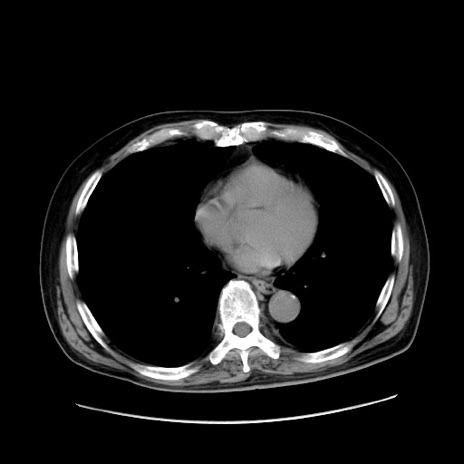

症例30(横断像)

【症例】80歳代男性

【主訴】臍周囲痛

【現病歴】約6時間前から臍下部痛が出現。次第に腹部膨隆・背部痛も生じてきたため来院。背部痛の場所は変化しない。

【身体所見】意識清明、BT 36.3℃、BP  131/87mmHg、P 87bpm、SpO2 100%(RA)、臍周囲自発痛・圧痛あり、反跳痛なし、自発痛部位に一致して板状硬あり、腹部膨隆、腸雑音減弱、CVA tenderness両側陰性。